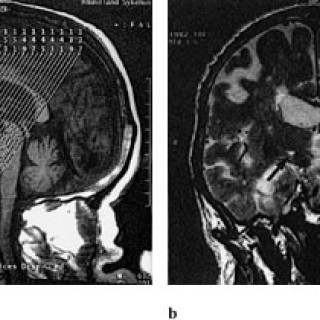

Gassemboli kan oppstå som følge av kirurgi, diagnostiske prosedyrer, traumer, lungeskader, bruk av hjerte-lunge-maskin og ved trykkfallssyke (1, 2). Gassemboli er en sjelden komplikasjon, men kan resultere i betydelig morbiditet, i verste fall død. Det er grunn til å tro at særlig iatrogen gassemboli i liten grad blir erkjent. Det er viktig at leger og sykepleiere i større grad blir oppmerksom på problemet, da de fleste pasientene vil kunne unngå sekvele med adekvat behandling. Med gassemboli menes vanligvis luftemboli, men med dagens bruk av andre gasser i medisinsk øyemed kan eksempelvis...